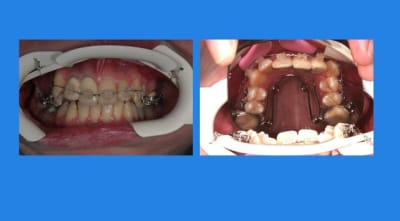

13/03/2010 à 23h42

4mois après, comme ça n’avance pas vite, pose Q.H

et pose du mat. Inf.

2 wqai8e - Eugenol

contrôle 3 semaines après

3 m607iq - Eugenol